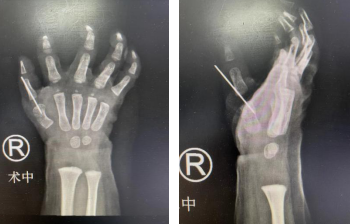

按照术前设计好的手术方案,设定右拇指尺侧指为主拇指,桡侧指为副拇指,李甲主任、滕道练副主任医师手术团队为患儿顺利矫形重建了右拇指。

术后即刻CT